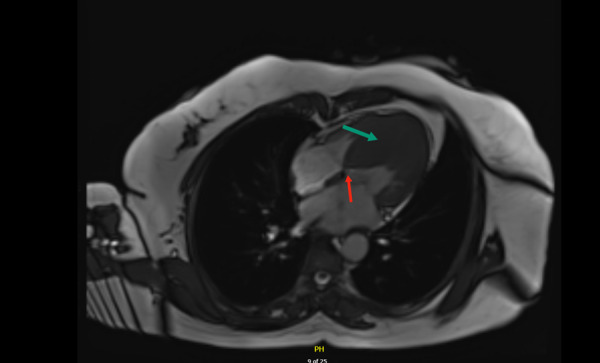

冠状动脉间通讯是一种罕见的先天性异常,定义为两条未闭冠状动脉之间的连接,于1972年首次被描述。我们报告的情况下,61岁的阿联酋女性谁提出了胸痛和心悸的急诊科,并与心脏疾病的强烈家族史。她最初被诊断为惰性肥厚性梗阻性心肌病并进行相应的治疗;然而,患者仍有症状。进一步的检查显示她的左旋冠状动脉(LCX)和左前降支冠状动脉(LAD)之间有冠状动脉间的通信。本病例强调了认识冠状动脉间通信对于HOCM患者更好预后的重要性,以及其潜在的临床意义,需要进一步研究以确定其真正意义。

Inter-coronary communication is a rare congenital anomaly, defined as a connection between two patent coronary arteries, and was first described in 1972. We report the case of a 61-year-old Emirati female who presented to the emergency department with chest pain and palpitations, along with a strong family history of cardiac disease. She was initially diagnosed with indolent hypertrophic obstructive cardiomyopathy and accordingly managed; however, the patient remained symptomatic. Further investigations revealed inter-coronary communication between her left circumflex (LCX) and left anterior descending (LAD) coronary arteries. This case highlights the importance of recognizing inter-coronary communications for better outcomes in patients with HOCM, as well as their potential clinical significance with the need for further studies to be done to pinpoint the true significance.